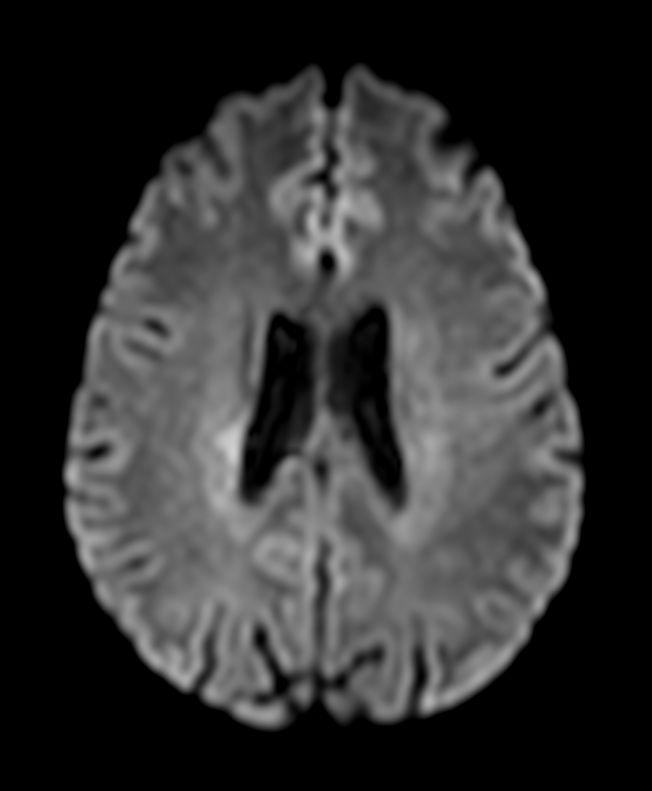

DWI b1000

DWI b1000 (ADC)